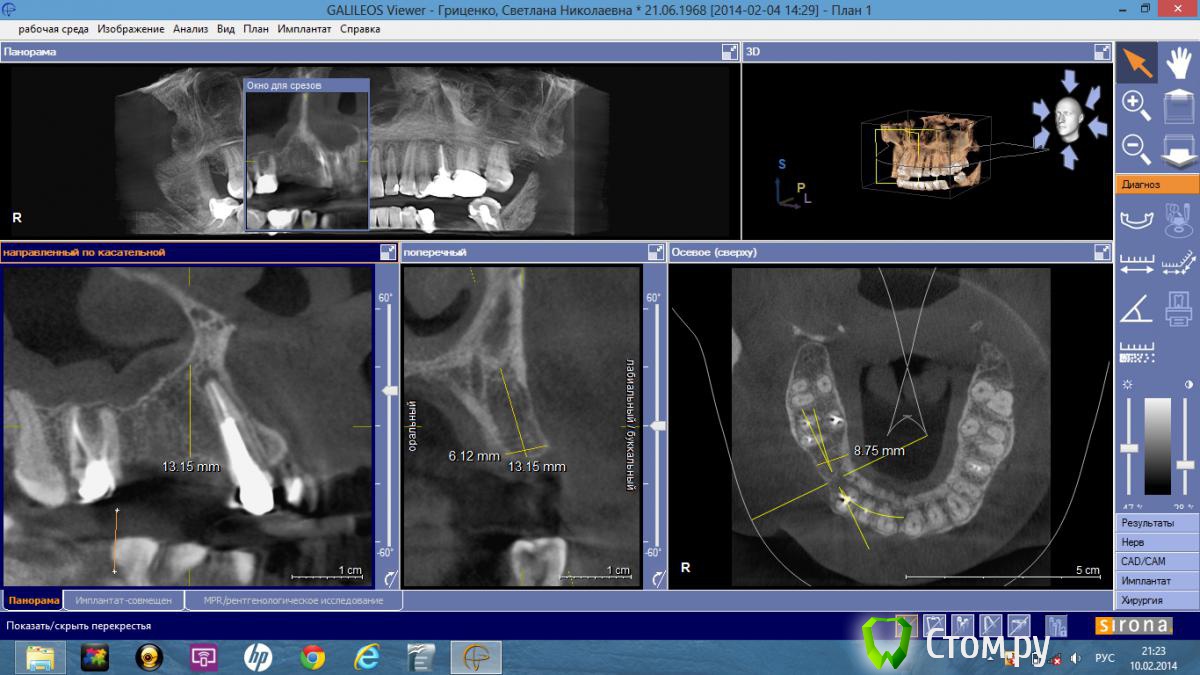

lavrikk Опубликовано 10 февраля, 2014 Поделиться Опубликовано 10 февраля, 2014 Добрый день коллеги! Планируется имплантация в области 1.4 и 1.5. Это моя первая операция на верхней челюсти, помогите с правильным позиционированием и выбором имплантантов. Использую систему Dentium, в области 1.5 хочу поставить 3.8 — 8 мм (без синуса, коронку в дальнейшем как моляр), в 1.4 - 3.4-10 мм. Как бы поступили Вы? Ссылка на комментарий

CToMaToJlor Опубликовано 10 февраля, 2014 Поделиться Опубликовано 10 февраля, 2014 (изменено) Смущают изменения на 13. В идеале надо бы с ними сначала разобраться. И 14 ближе к клыку сместить( имеется в виду риска на модели). Удачи! Изменено 10 февраля, 2014 пользователем CToMaToJlor Ссылка на комментарий

bullbull Опубликовано 11 февраля, 2014 Поделиться Опубликовано 11 февраля, 2014 Сделал бы 10 мм с закрытым синусом. Направление более вертикально.Что касается 13: подумал бы о повторном эндо и резекции одновременно с имплантацией. 2 Ссылка на комментарий

lavrikk Опубликовано 11 февраля, 2014 Автор Поделиться Опубликовано 11 февраля, 2014 А также как вы относитесь по поводу вмешательств на синусе при таких изменениях в пазухе? Ссылка на комментарий

bullbull Опубликовано 12 февраля, 2014 Поделиться Опубликовано 12 февраля, 2014 В 13 вкладка. Извлечь ее и ортоградно перелечить не представляется возможным. Резекцию лучше проводить одновременно с имплантацией? Просто к разрезу по гребню добавить полулунный в области верхушки или добавить один вертикальный? Для закрытого синуса нет даже остеотомов.какие в этом случае необходимо-вогнутые диаметра имланта? Когда вы начинали многоуважаемые доктора, случались ли у вас в дальнейшем осложнения при установке 8 мм без синуса в этой области?Спасибо за добрые советы!Тогда на 15 3,8х8 мм, на 14 - 3,4х12. Выбор остеотомов зависит от качества кости. Если очень мягкая, то можно после пилота (2-2,5 мм) расширять только остеотомами. Для диаметра 3,8 остановился бы на остеотоме 3,5, при 3,4 - 3,0. Осложнений быть не должно. Прогноз благоприятный. Если торк больше 35, можно заканчивать ФДМ или коронками.При подобных изменениях поднятие на 2 мм не смертельное. Хотя, иногда слизистая бывает рыхлая и просто прокалывается остеотомом. В такой ситуации на дно костного ложа кладу ОбТП и ставлю винт. Ссылка на комментарий

DShu Опубликовано 12 февраля, 2014 Поделиться Опубликовано 12 февраля, 2014 А также как вы относитесь по поводу вмешательств на синусе при таких изменениях в пазухе?Такая слизистая меня даже радует-ни за что не порвется) делайте закрытый синус 1 Ссылка на комментарий